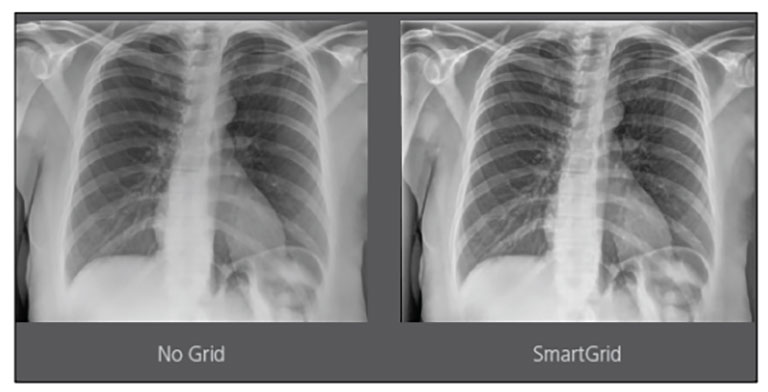

CARESTREAM Image Suite V4 MR11 has set a new standard for workflow efficiency, offering a robust set of features and functionalities to enhance clinical confidence in healthcare professionals. Using an auto-generated companion image from a single exposure, leverage a range of image processing options to increase diagnostic accuracy and enhance patient care.